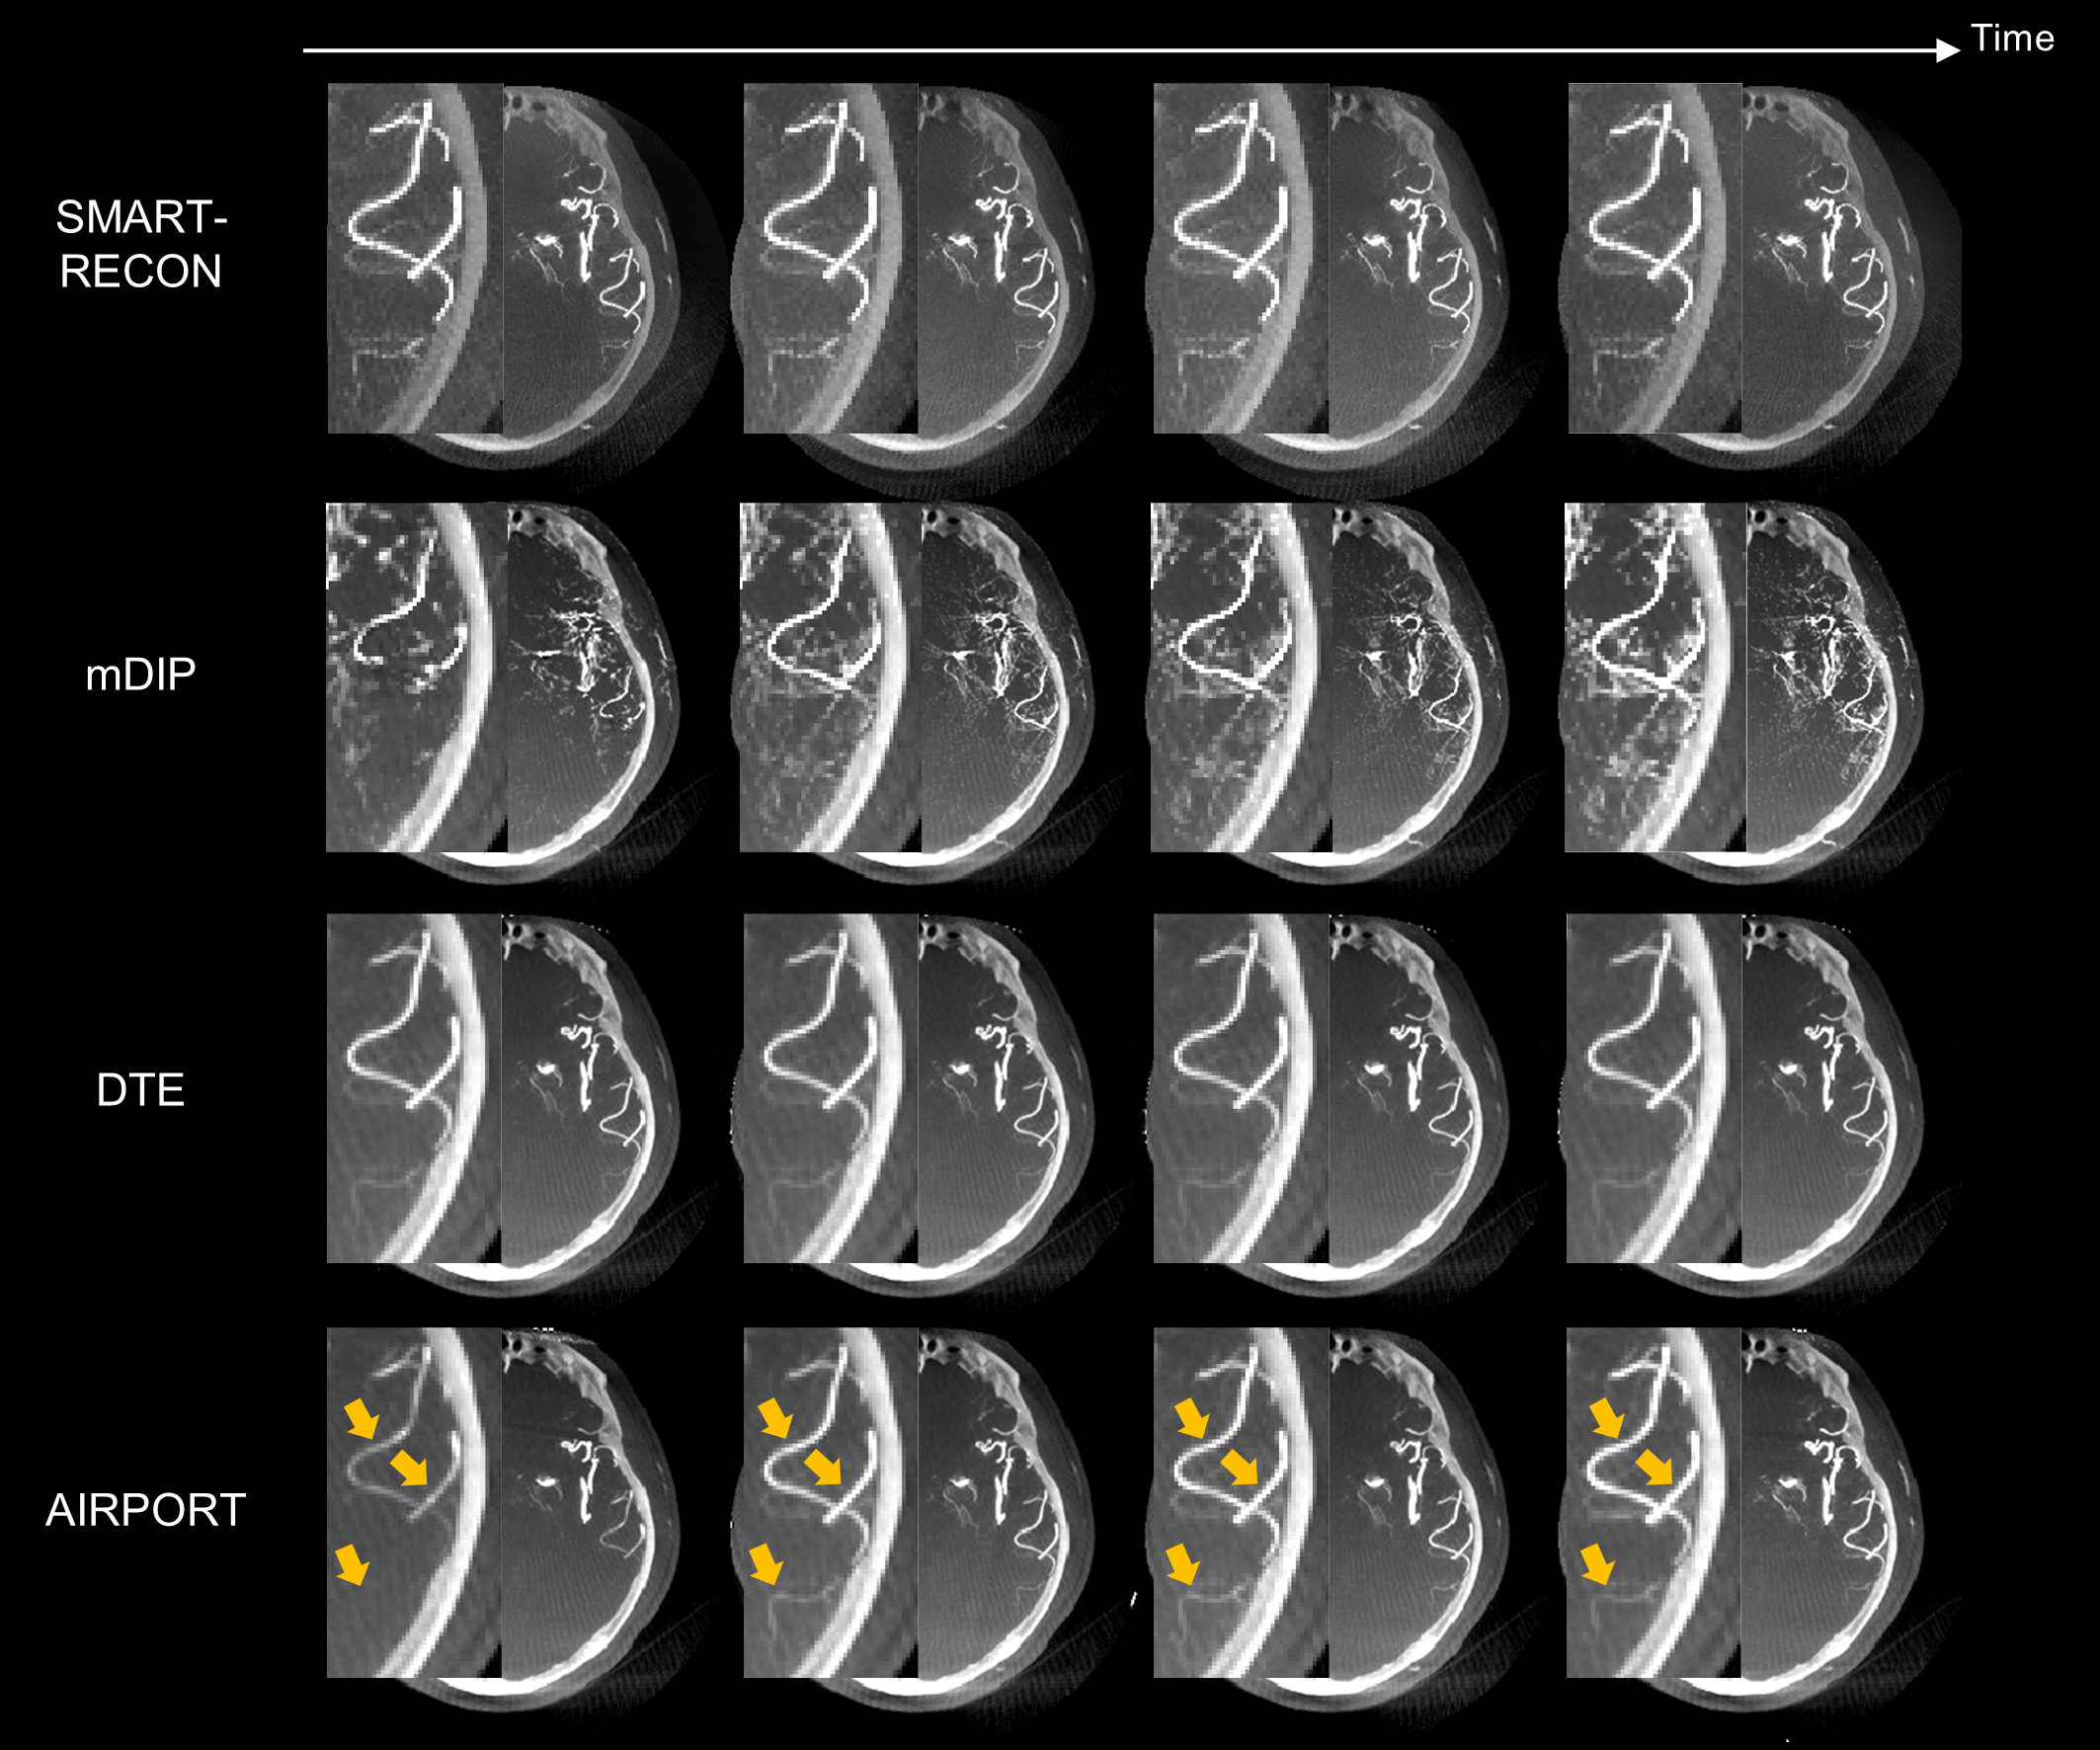

3. 人体实验数据结果如黄色箭头所示,提出的AIRPORT方法能够正确地重建由造影剂注射导致的动脉强度值的变化。